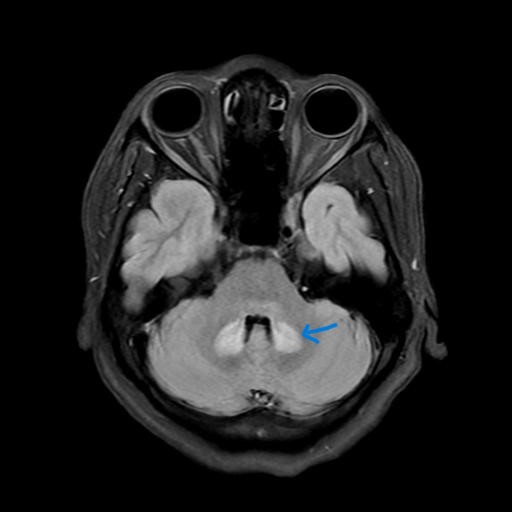

Gần đây khoa Thần kinh, Bệnh viện Hữu nghị đa khoa Nghệ An tiếp nhận một số ca bệnh tổn thương não nghi ngờ liên quan đến việc sử dụng thuốc lợi sữa không rõ nguồn gốc. Bệnh nhân nữ 41 tuổi, vào viện vì đau đầu, tê bì tay chân. Bệnh nhân sau sinh cách 1 tháng, có sử dụng thuốc lợi sữa không rõ xuất xứ. Khoảng 5 ngày nay, xuất hiện tình trạng đau đầu, nhìn một hình thành hai hình, tê bì tay chân, chóng mặt,mất thăng bằng, đi lại khó khăn. Chụp phim cộng hưởng từ não có hình ảnh tổn thương cầu não, hành não, tiểu não đối xứng hai bên. Đây là hồi chuông cảnh báo nghiêm trọng cho các bà mẹ sau sinh.

Hình ảnh phim chụp cộng hưởng từ (MRI) của bệnh nhân